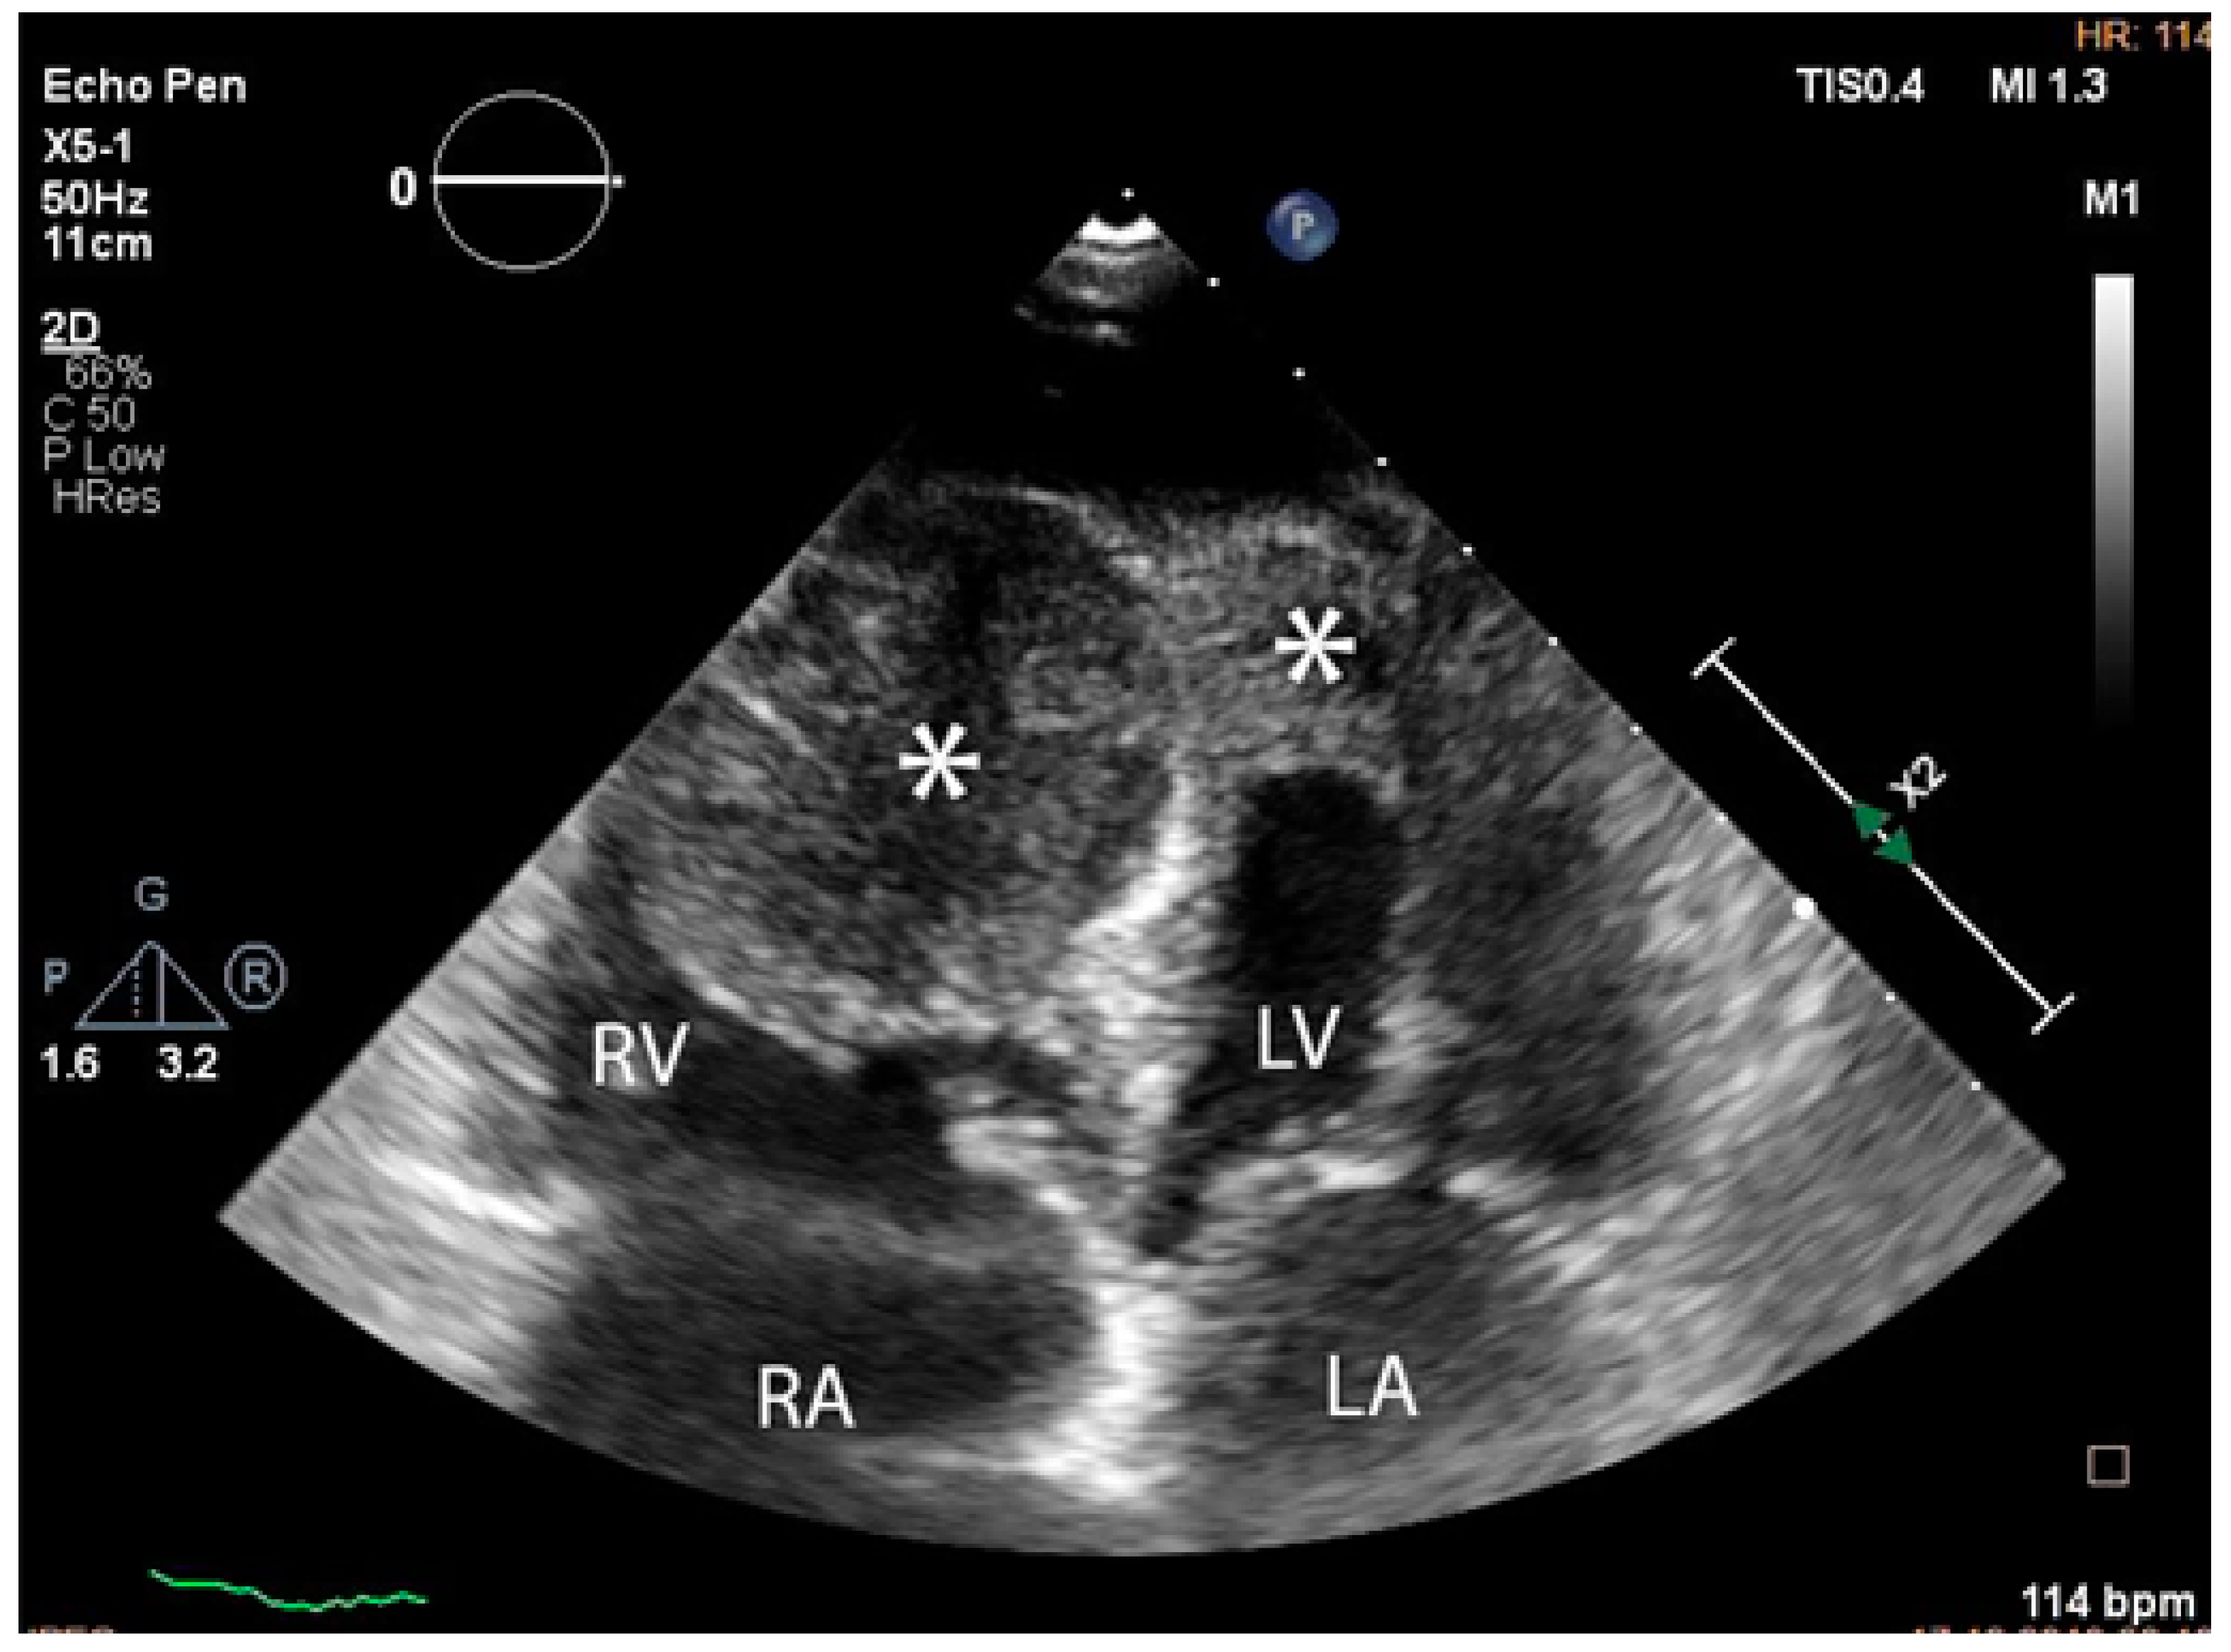

The troponin I level was found to be slightly elevated (90 ng/mL). Coronarography was used to rule out any luminal or anatomical abnormalities. A tumour filling the right ventricle and involving the apex of the left ventricle was identified at transthoracic echocardiography (Figure 3 and Figure 4).

Figure 3. Transthoracic echocardiographic apical four-chamber view: a larger mass (∗) in the right ventricle which also involves the apex of the left ventricle. (Abbreviations: RA = right atrium, LA = left atrium, RV = right ventricle, LV = left ventricle, (∗) cardiac mass.)

Diagnostics 14 00919 g003

Figure 4. Transthoracic echocardiographic, biplane view of the right ventricle; note the mass (∗) that displaces a significant part of the cavity. (Abbreviations: RA = right atrium, LA = left atrium, RV = right ventricle, LV = left ventricle, (∗) cardiac mass.)

Diagnostics 14 00919 g004